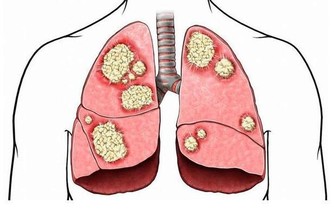

木耳它含有的可溶性膳食纖維,可以促進腸道蠕動,預防高血脂,是一款不錯的潤肺排毒食物。

西蘭花西蘭花中含有的吲哚和硫氰酸鹽等有益成分,可以幫助清除體內毒素,減小腎臟負擔,

並且有助預防癌症。